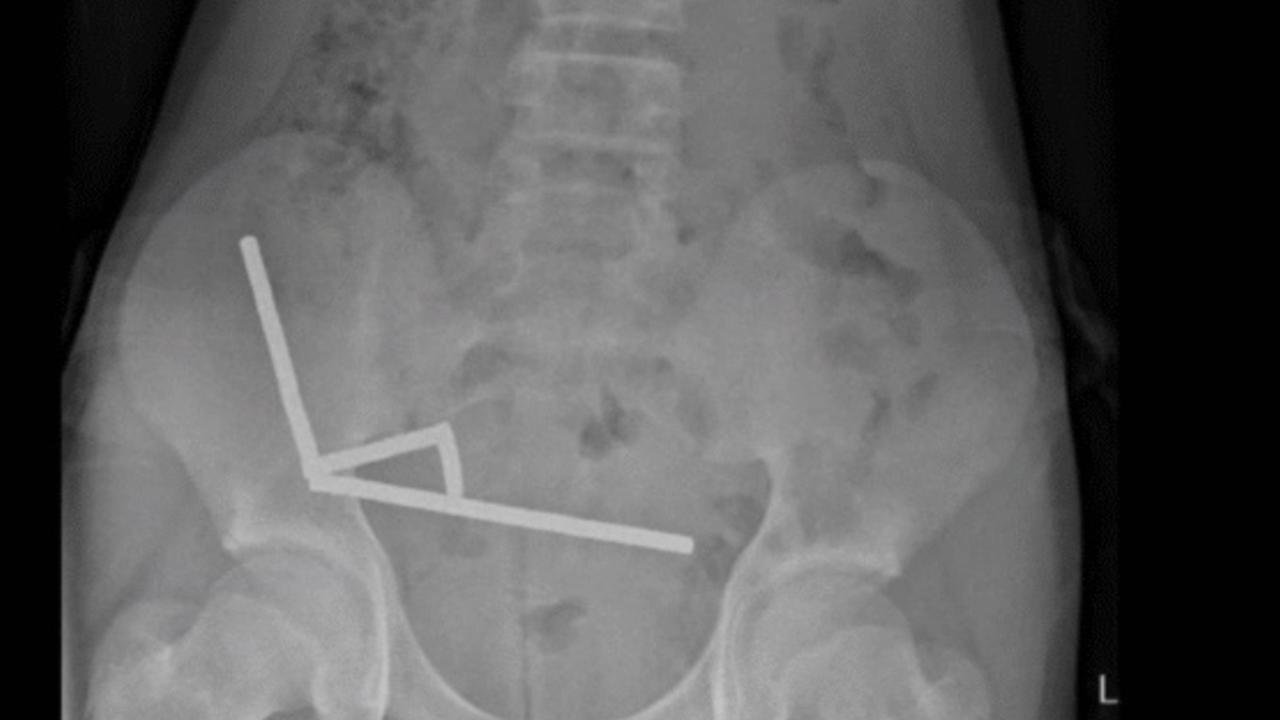

Röntgen görüntülerinde, çocuğun bağırsağında dört ayrı bölgede zincir halinde dizilmiş metal toplar görüldü. Ameliyatta bu zincirlerin ince bağırsak ve çekumda (kalın bağırsağın başlangıcı) birbirine yapışarak dokularda kan akışını engellediği ve “basınç nekrozu” denilen doku ölümüne yol açtığı tespit edildi.